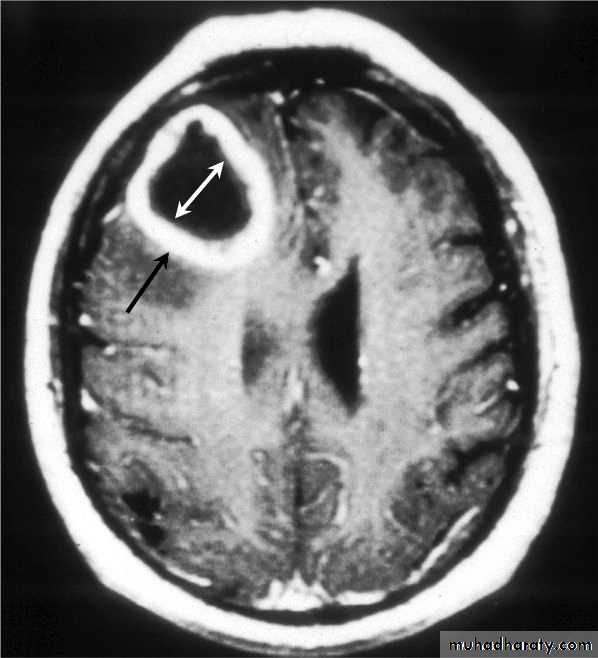

Brain Abscess CT with contrast

د.عبدالرحمن

• CT or MRI is the investigation of choice.

• They will show a single (or multiple) space occupying lesion that is well delineated with an enhancing wall, with variable surrounding oedema.

• The differential diagnosis of a single brain abscess in CT or MRI is a solitary metastasis, primary brain tumour or cerebral infarction.